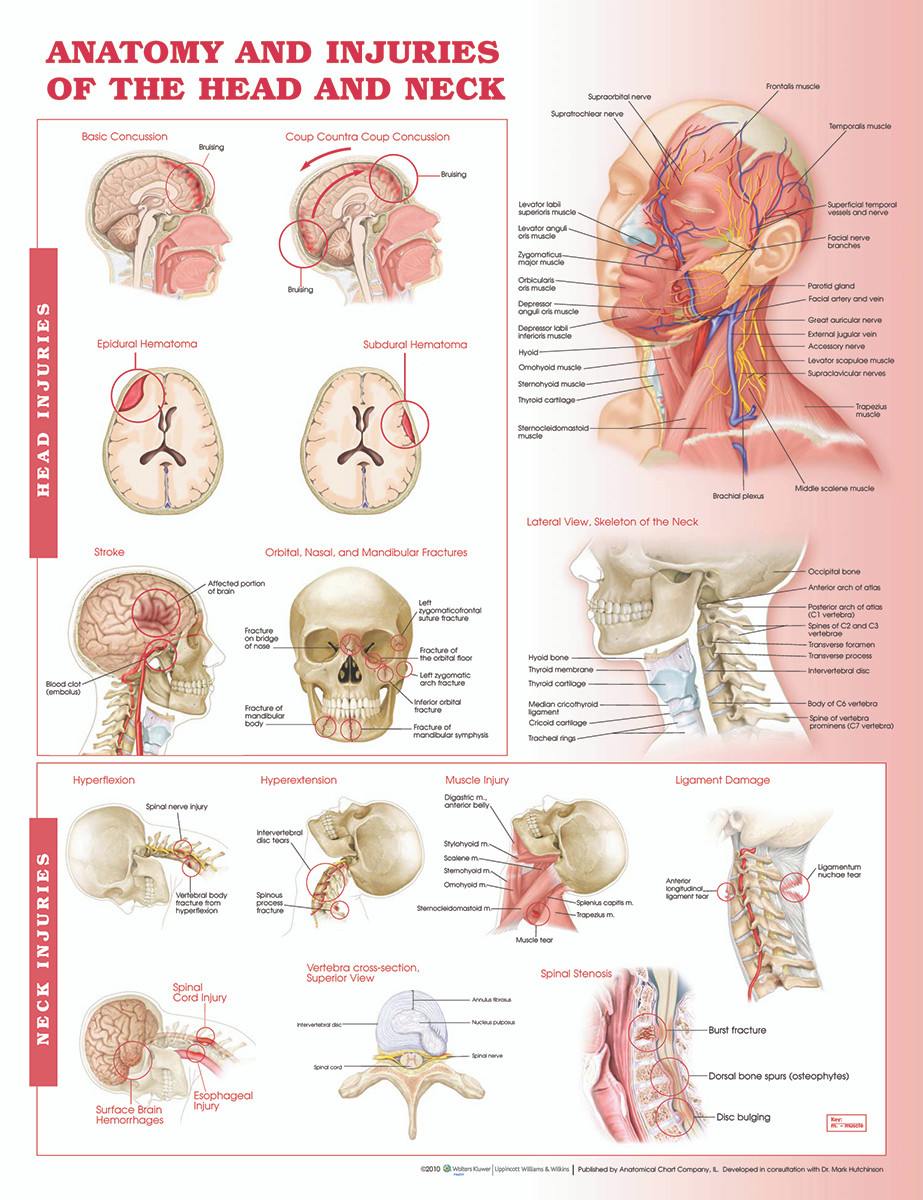

Reference Chart Anatomy and Injuries of the Head and Neck

Understanding the Head & Neck Scientific Publishing

The gross anatomy of the head and neck lecture 3